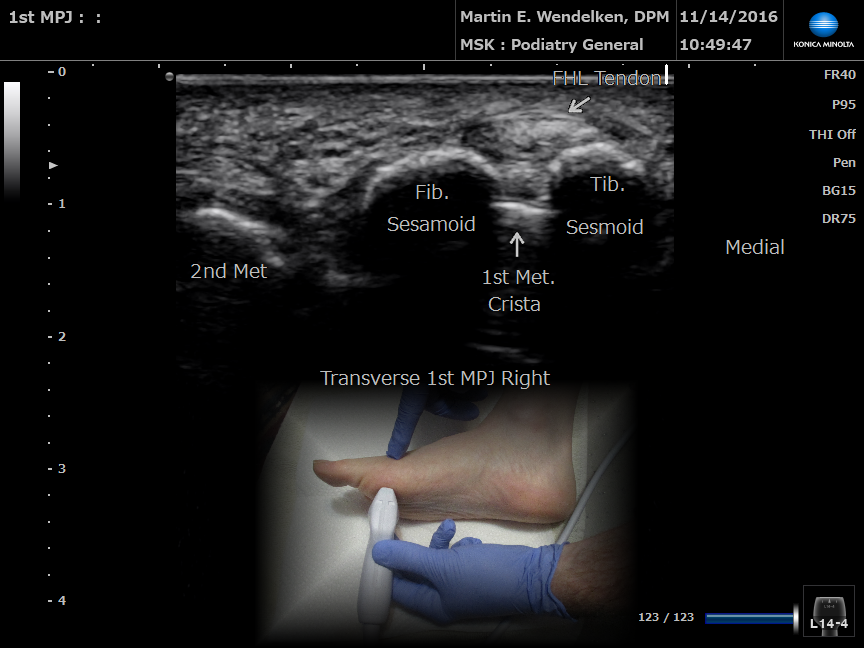

• Image 1: 1st Metatarsal Phalangeal Joint

• Image 8: Transverse 1st MPJ